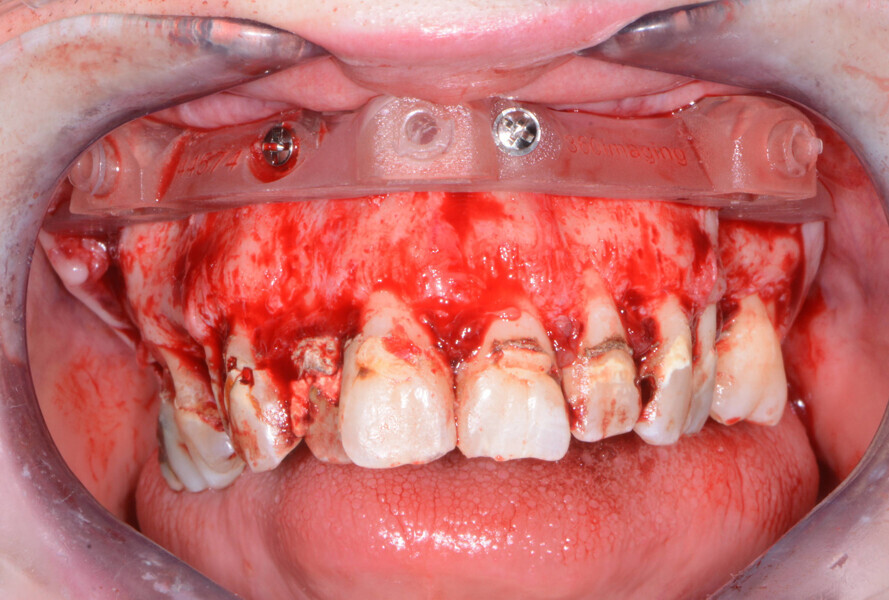

Once the virtual plan had been orchestrated by the laboratory and fully confirmed by me, the next appointment was for the planned surgery with all the necessary components for the guided surgical approach. The patient was appropriately sedated with intravenous medications, and local anaesthesia was administered in both arches. The tissue was then reflected using the Reflector instrument (GoldenDent) so that the bone levelling surgical guide would be fully seated and fixed with its respective retention screws (Figs. 6 & 7). After the positioning of the surgical guide, the maxillary teeth were atraumatically extracted from anterior to posterior utilising the Physics Forceps (GoldenDent). Using a bone reduction bur in the surgical handpiece and motor (Aseptico) with ample irrigation, the maxillary ridge was trimmed to the level indicated by the guide. Once the appropriate bone levelling had been accomplished with the surgical handpiece, the implant surgical guide (Fig. 8) was positioned into the bone levelling guide and the osteotomies for the implants were initiated with a designated pilot drill in the implant system’s guided surgery drilling kit (Adin Dental Implant Systems; Fig. 9).

Fig. 6: Positioning guide.

Fig. 7: Maxillary bone levelling foundation guide.